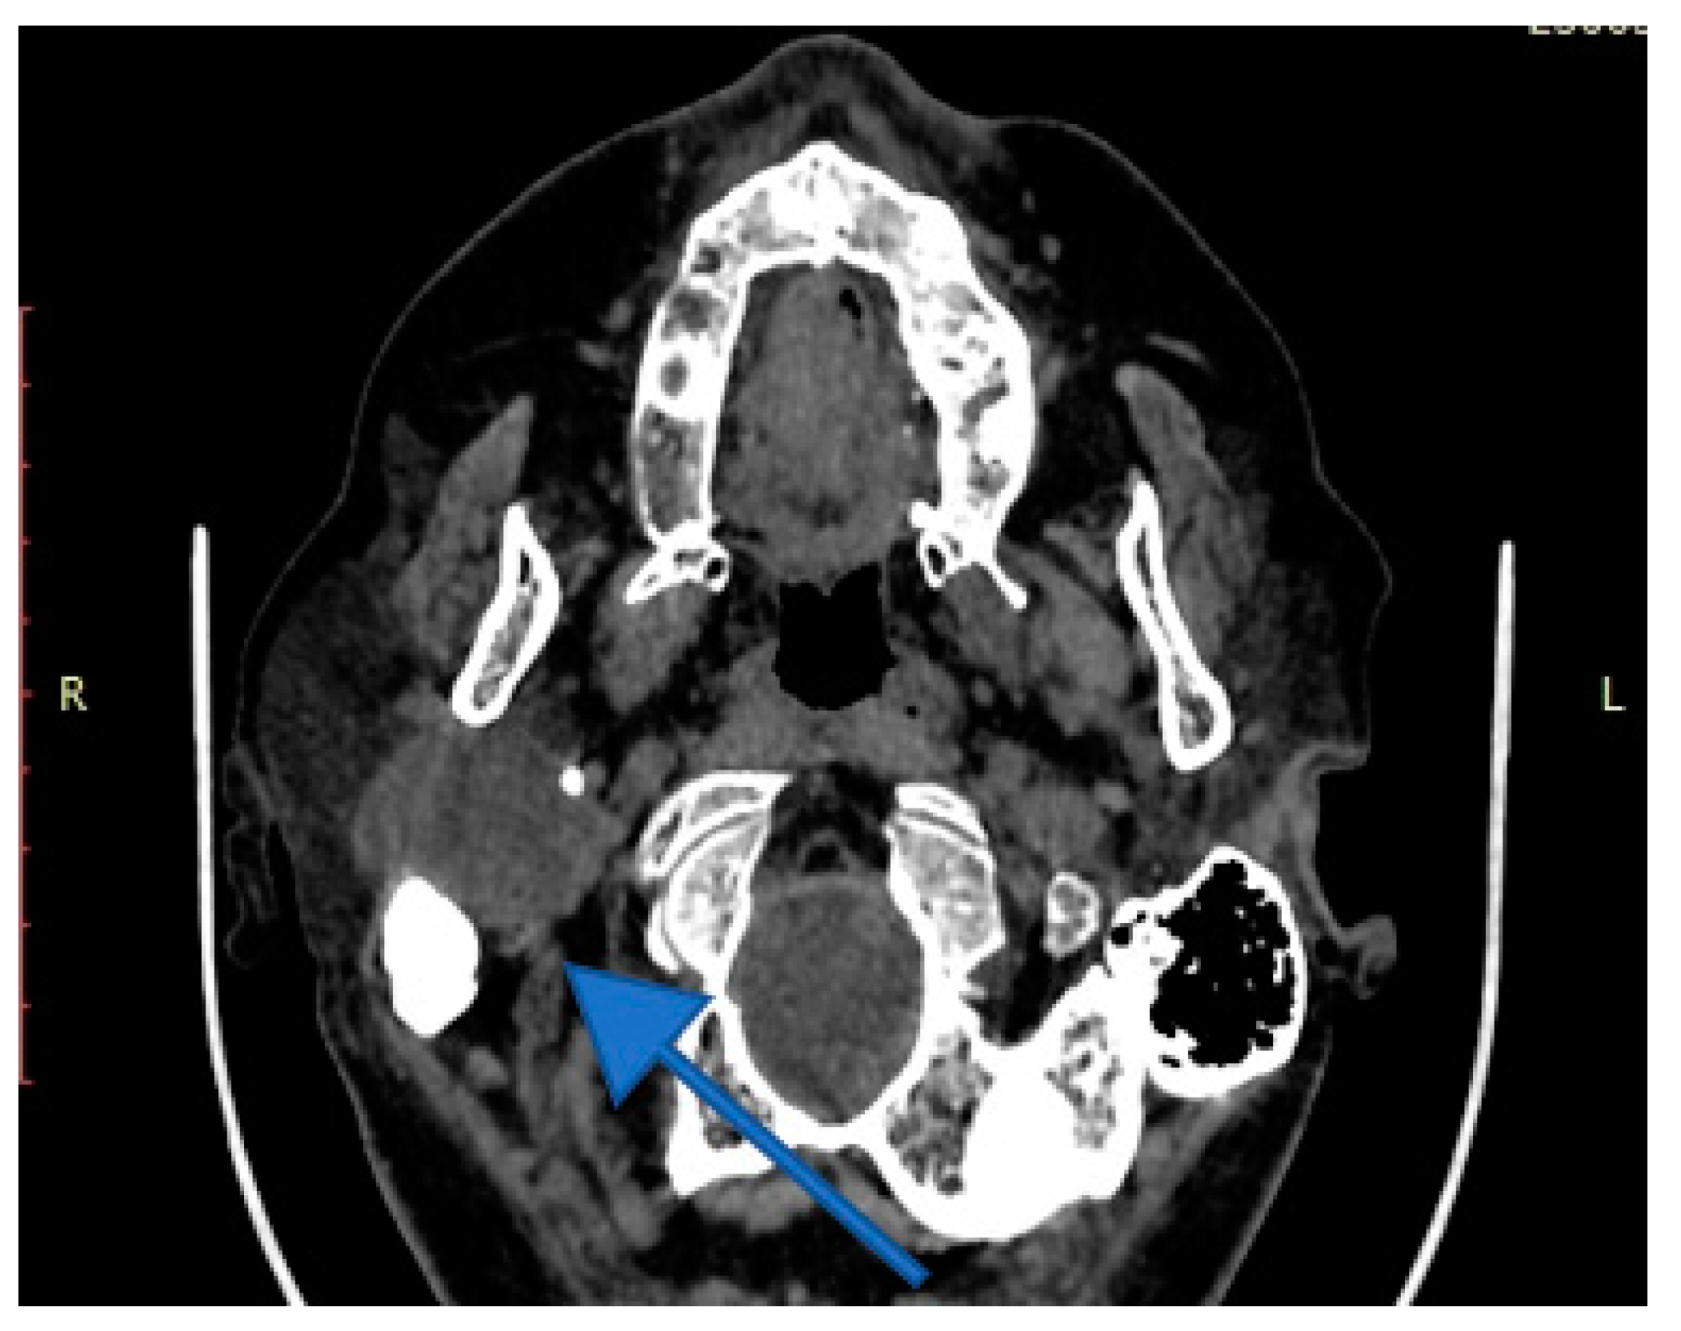

4. Imagery in Extracranial FNSs